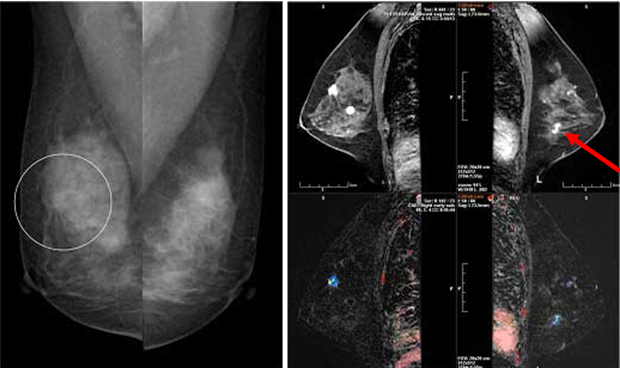

계적으로 여성은 3명 중 1명이 암에 걸린다고 합니다. 여성암 중 갑상선암 다음으로 두 번째로 높은 암이 유방암이라고 하는데, 중년 여성의 암 사망률로는 유방암이 1위라고 합니다. 유방암이란 유방에 나타나는 모든 악성 종양을 통틀어 말하는 것으로 보입니다. 유방암은 유방에 비정상적인 조직이 계속 자라거나 다른 장기에 퍼지는 위험한 병이라고 할 수 있습니다.